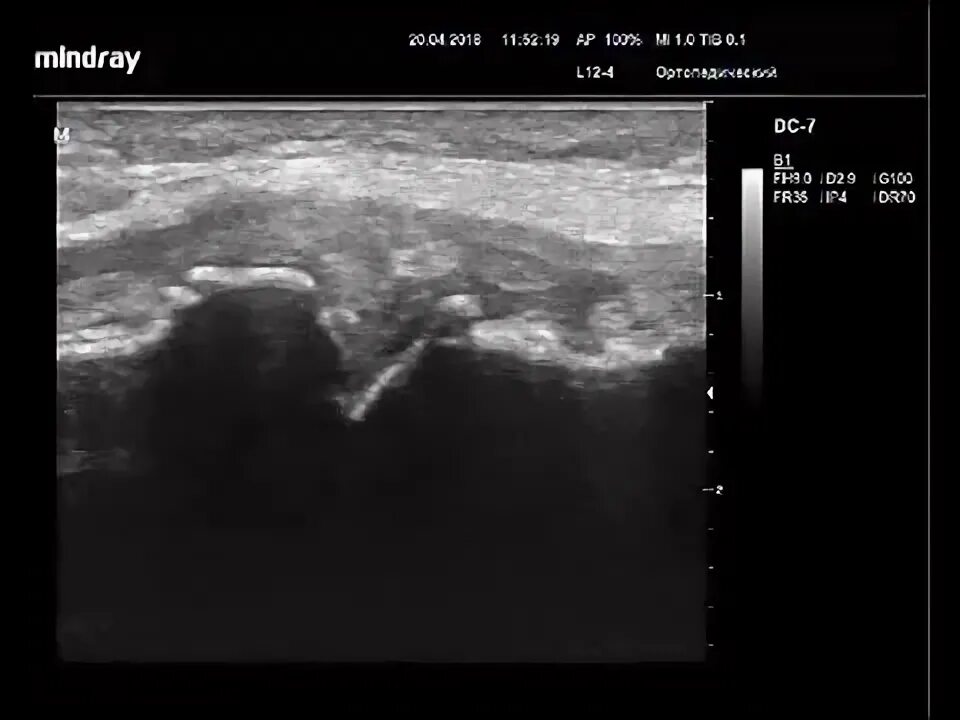

Синовит дегенеративные изменения медиального мениска